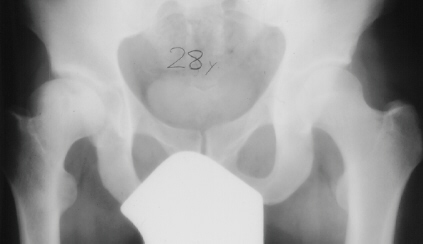

At 28 years of age, he had been having increasing pain in his right hip. He had a limp when he was tired. Positive Trendelenburg's sign was observed on the right. Internal rotation was limited to 25 degrees. All other motions were normal. X-ray showed cystic change. At the 29 years of age, he underwent bone graft of the right femoral head for degenerative cyst. At 35 years of age, only internal rotation was limited to 20 degrees. He still had pain in his hip that relates primarily to weather or to excessive walking. Only internal rotation was limited to 20 degrees. He had hip pain at the extremes of flexion and internal rotation. X-ray showed the progression of the cystic change. CT which was performed because of the question of loose bodies in the hip did not seem likely that the densities were actually in the hip joint. The antero-medial location of the cysts facing the anterior margin of the acetabulum was well depicted in CT.

28 yrs, 29 yrs, 30 yrs, 35 yrs .